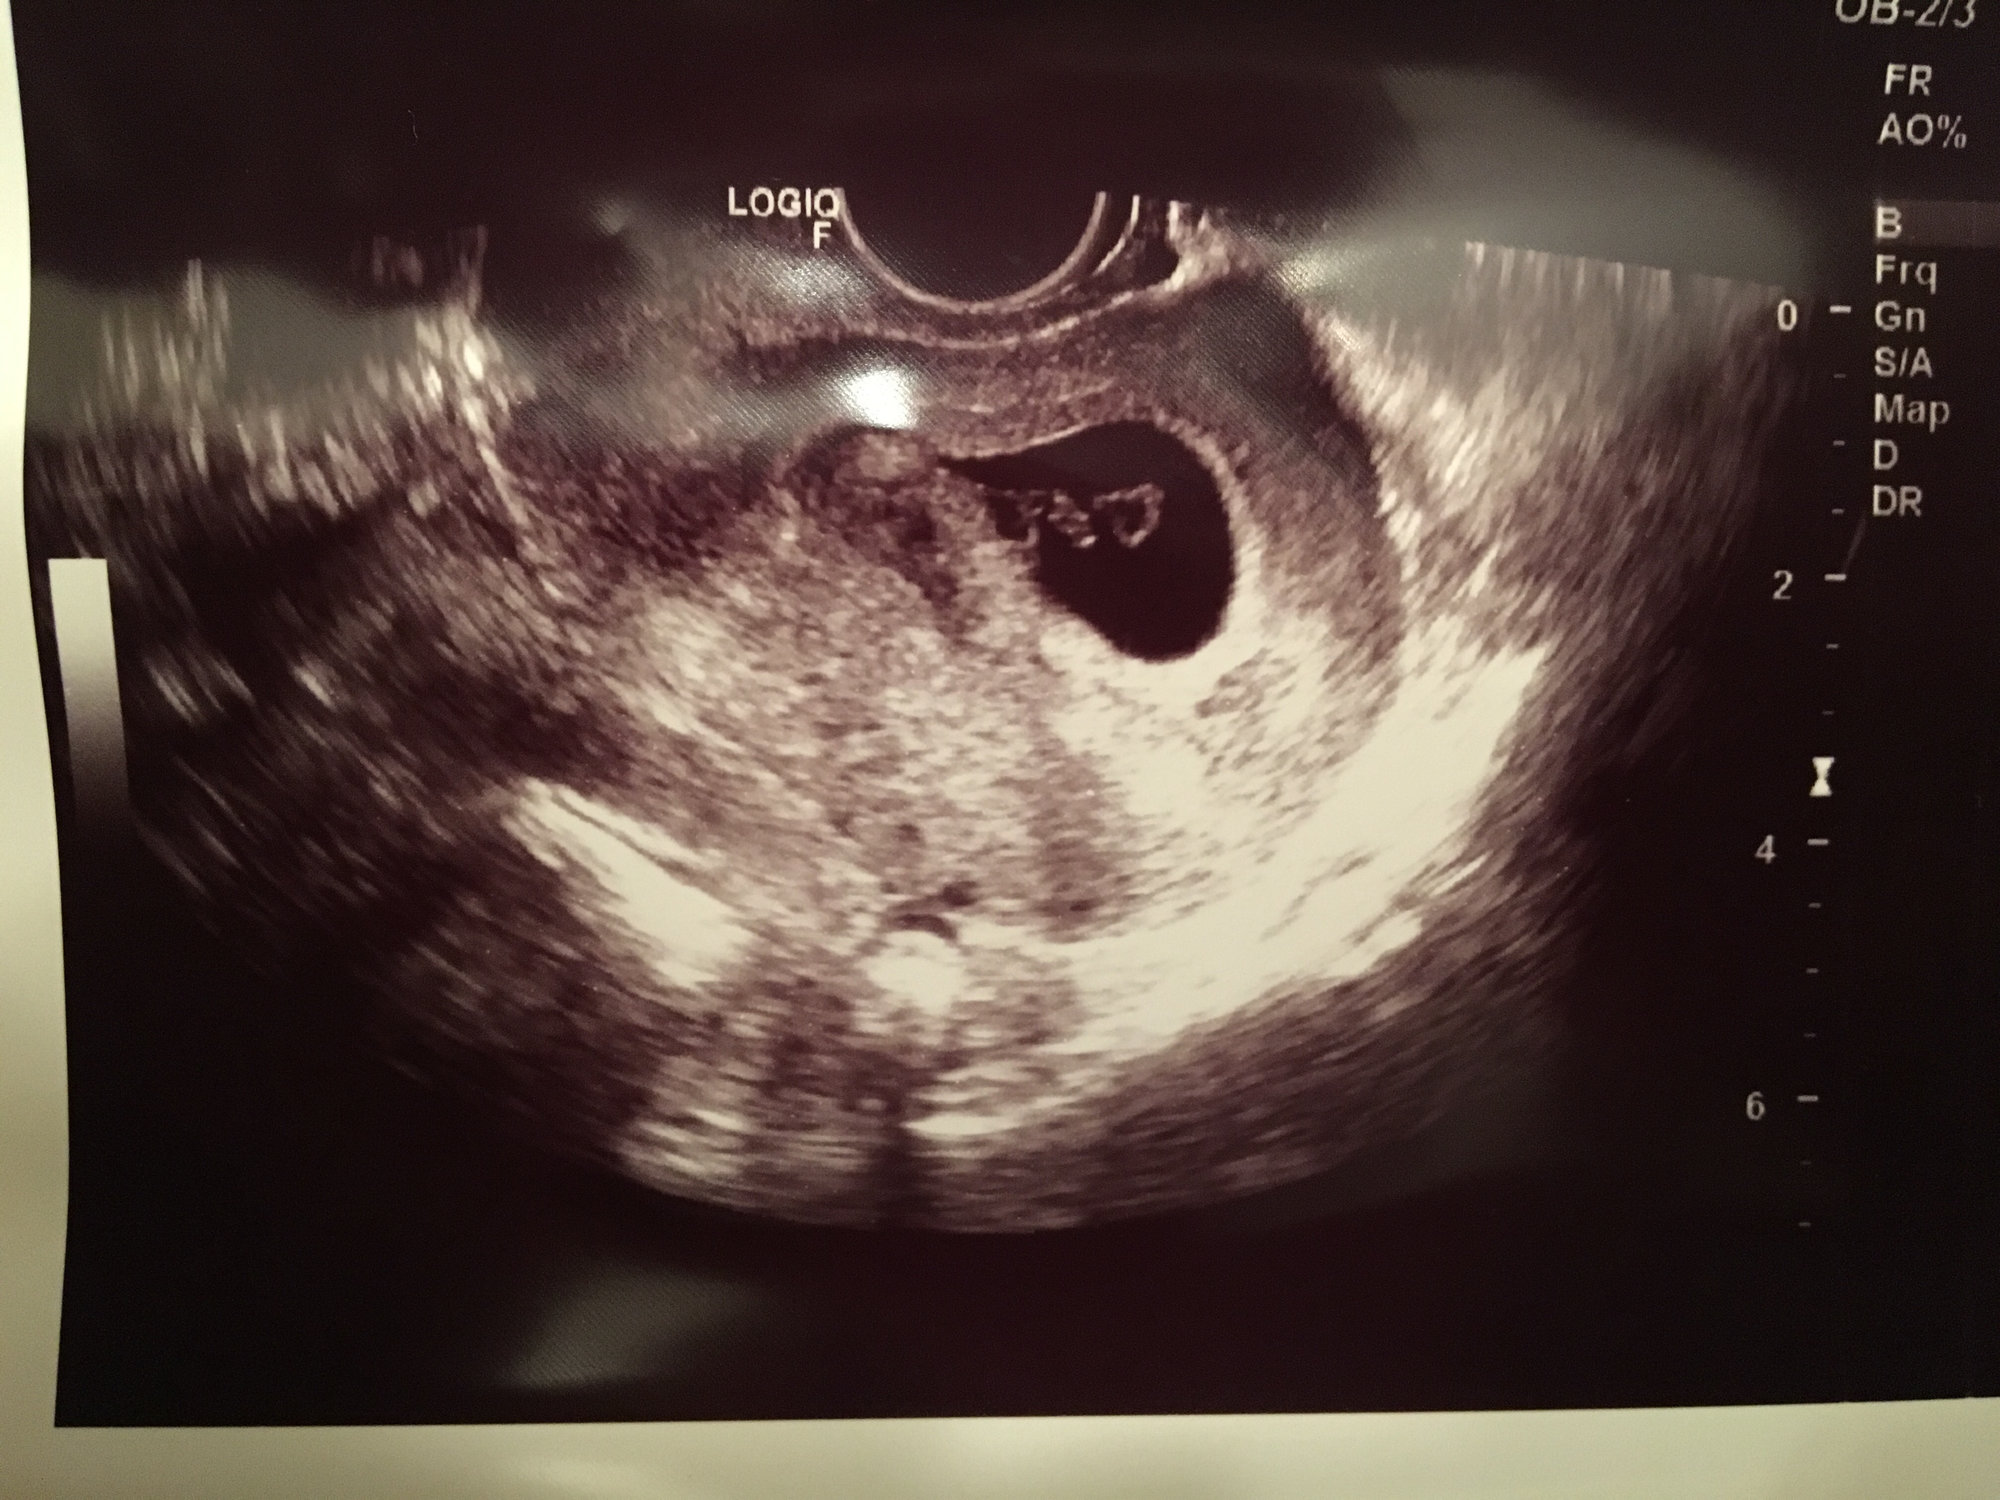

I'm a double loss momma, so my specialist is monitoring me closely. All of my betas have been increasing well and I had my first ultrasound today. The dr dated me at 6w+2 (I thought I was 6w+5, but maybe little one took a few days to implant.)

got to hear the heartbeat today too! It was such a gift to get to hear it. Heart rate was 122 and so far everything looks good. He said if I can make it two more weeks my loss chance goes down significantly. Next ultrasound at 8 weeks.